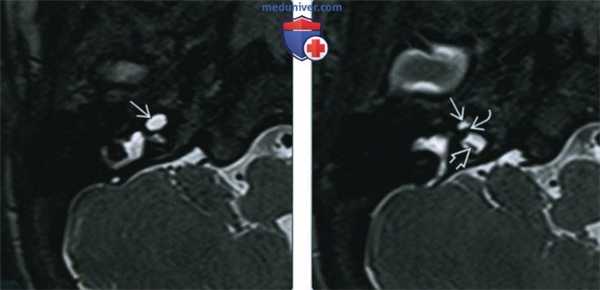

Один пациент, по данным КТ височных костей, имел двустороннюю облитерацию лабиринта, включая улитки с двух сторон, с большей выраженностью патологических изменений справа. На МРТ было выявлено уменьшение количества жидкости в улитке справа, слева количество жидкости в улитке соответствовало норме (рис. 1, 2).

Рис. 1. КТ, аксиальная проекция. Облитерация улитки (стрелка).

Рис. 2. МРТ, аксиальная проекция. Справа — полное отсутствие жидкости в улитке (короткая стрелка), слева — частичное (длинная стрелка).